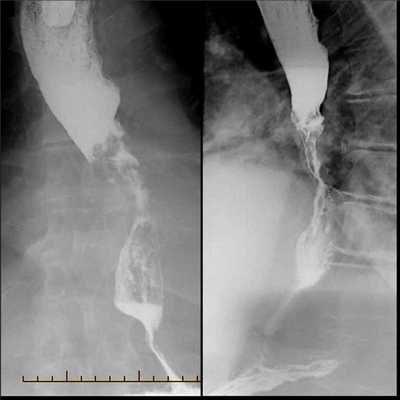

(Слева) На рентгенограмме определяется сужение просвета дистального сегмента пищевода в виде «огрызка яблока». Это переходная зона между проксимальной частью опухоли и неизменной частью пищевода. Слизистая оболочка в области опухоли разрушена, имеет узловатый вид.

(Справа) На рентгенограмме этого же пациента видны узло-видно утолщенные складки слизистой в области кардии, что позволяет предположить распространение опухоли на желудок. Кроме того, можно также предположить распространение рака желудка в дистальные отделы пищевода.

о Неравномерное сужение просвета пищевода, проксимальный и дистальный края резко обрываются

о Крупное объемное образование с дольчатым контуром в просвете пищевода

(а) Пациент, страдающий раком пищевода, обратился с жалобами на дисфагию. При рентгенографии органов грудной клетки в ПП проекции в нижних отделах средостения определяется объемное образование, на фоне которого азигоэзофагеальный карман и левый парааортальный контур не визуализируются.

(б) У этого же пациента при рентгеноконтрастном исследовании пищевода в боковой проекции визуализируются расширение проксимальных отделов пищевода и выраженное неравномерное сужение его просвета. Дистальный и проксимальный края суженной части пищевода резко обрываются. Данная картина соответствует объемному образованию в просвете пищевода.